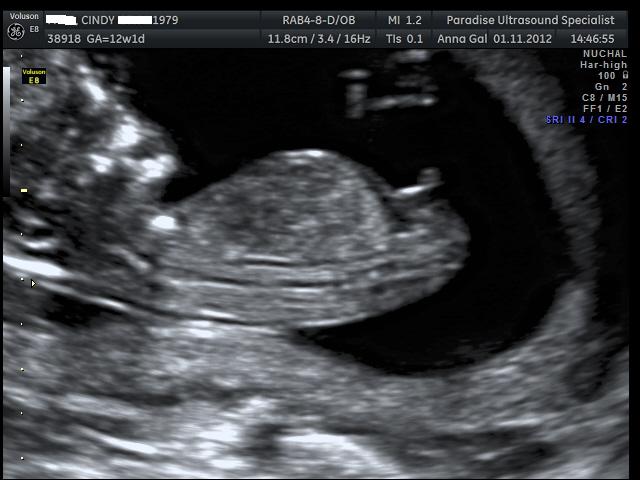

Here are the pics from my NT scan, the tech had a guess she said she is 70% positive the sex is.... can you guess? UPDATE - It's a boy :)

I'm no expert but that looks like a boy to me!!

That is a BOY! huge congrats to you cinss.... And Omg I can not believe you are already 12 weeks!